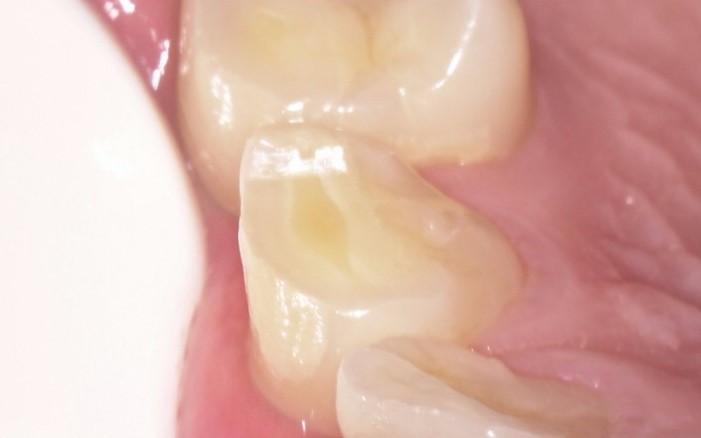

虫歯ができやすい箇所

カリエスの好発部位に裂溝部分があります。 これは歯の溝の部分に磨き残しがありそこが虫歯ができやすい部分になります。今回は拡大鏡をつかってその虫歯の部分をきれいになおした動画を作ったのでよかったらみてください。 簡単な虫歯 […]